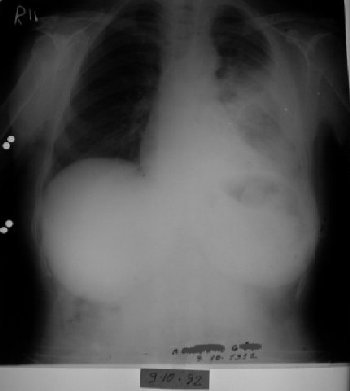

1995 yılında küçük hücreli anaplastik karsinom teşhisi konulan 31 yaşındaki erkek hasta, kemoterapiyi reddederek immünomodülatör tedavi ile 7 ayda tam iyileşme sağladı. Şiddetli ağrıları sadece 12 günde kayboldu ve röntgende tümör tamamen ortadan kalktı.

1995: 31 yaşındaki erkek hasta öksürük, ateş ve sırt ağrısı ile başvurdu.

Biyopsi sonucu "küçük hücreli anaplastik karsinom" teşhisi kondu.

24 Ekim 1995: Hasta uzman hekime getirildi.

4 mg immünomodülatör aşı sonrası ateşi 38.2°C'ye yükseldi.

Tedavi Protokolü: Haftada 6 gün, 4 mg immünomodülatör aşı

12 gün sonra: Şiddetli ağrıları tamamen kayboldu.

Röntgende kitle küçülmüş durumda görüldü.

Röntgen tümörün tamamen kaybolduğunu gösterdi.